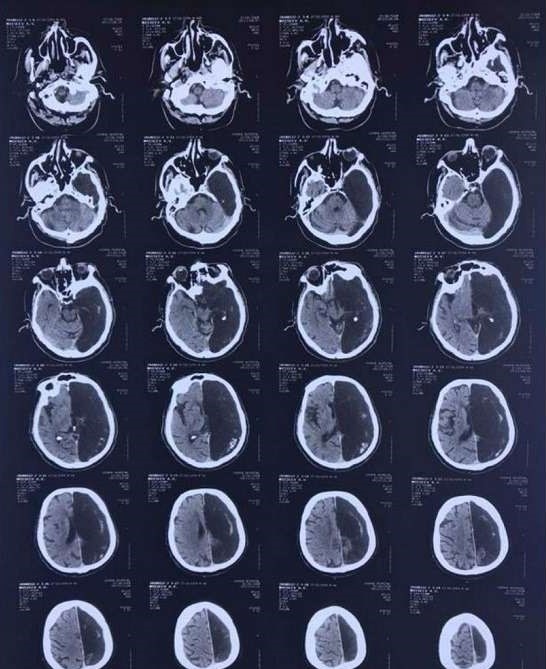

Житель Подмосковья 60 лет прожил без половины мозга

60-летний житель Подмосковья прожил всю жизнь без левого полушария. Это было обнаружено случайно при подозрении на нарушение мозгового кровообращения, близкое к инсульту. Пациенту сделали компьютерную томографию, которая показала, что части мозга, в которой случилось нарушение, просто нет!

Оказалось, что мужчина не испытывал от этого никаких неудобств. Отсутствие половина мозга не помешало ему окончить вуз, отслужить в армии и проработать инженером до самой пенсии. У него есть жена и дети. За всю жизнь у него не было проблем с психикой, и вообще к врачам обращался редко, поскольку отличался завидным здоровьем.

В больнице симптомы транзисторной ишемической атаки, как называется это расстройство по-научному, прошли быстро. Подвижность руки и ноги на стороне тела, за которую отвечает отсутствовавшее полушарие, восстановились за считанные дни.

Пациент выписался, оставив врачей в недоумении. А от обследования отказался. Зачем, если это ему никак не мешало до сих пор. Просил и не упоминать даже имя, сославшись на то, что слава ему не нужна.

К счастью, такая особенность по наследству не передаётся, поскольку чаще всего возникает ещё до родов. Обычно заканчивается выкидышем, но бывает, оказывается, и так.